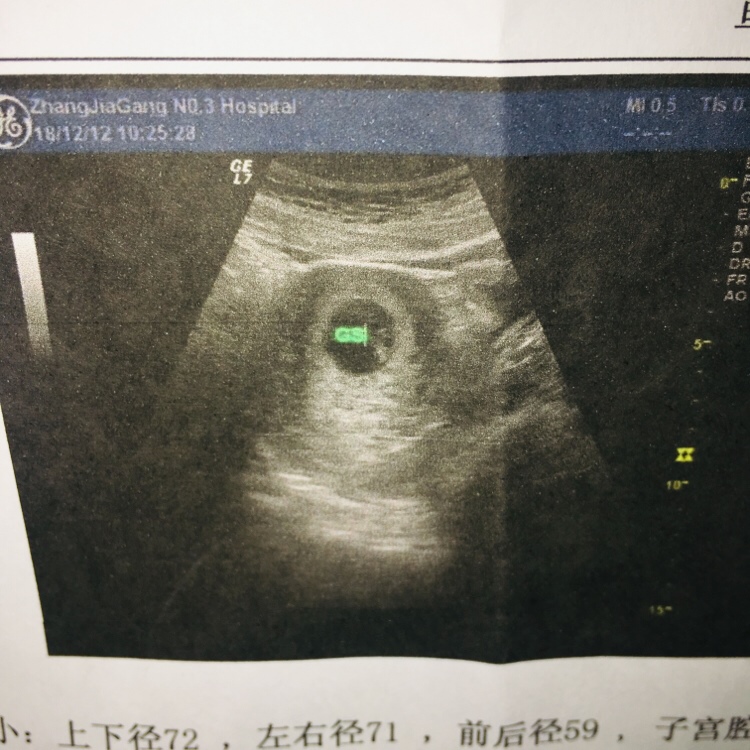

孕5周+6天